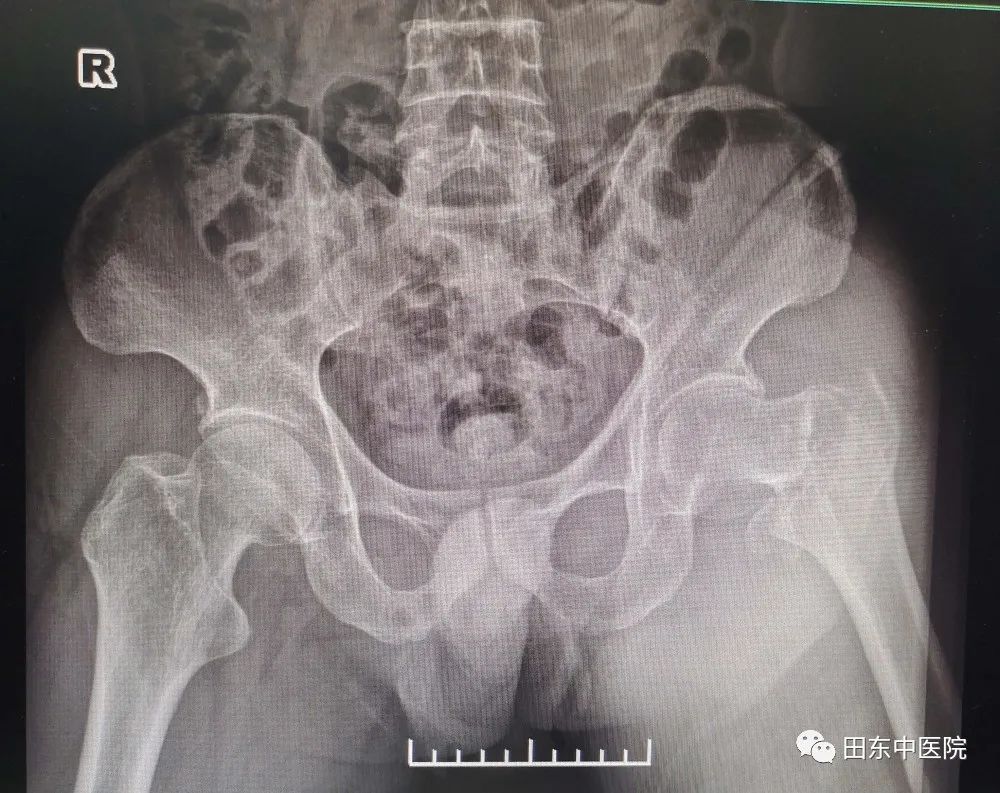

患者于5月24日因跌伤致左髋部疼痛来诊。入住我院骨伤科。入院后完善相关检查诊断为:1.左股骨粗隆间骨折 2.慢性肾脏病5期 3.肾性贫血 4.肾性高血压 5.右侧丘脑、左侧额叶及左枕叶脑梗死6.痛风。影像显示:左侧股骨粗隆间见不规则清晰骨折线,骨折端对位、对线不良,骨折远端向上移位,局部形成骨碎片。骨科一病区罗张进主任诊查病人后指出:患者诊断明确,有手术指征。可行闭合复位复位髓内钉内固定微创手术治疗,此方案术中损伤干扰小,出血少,内固定牢固,愈合快,功能恢复好。但患者有肾脏疾病及脑血管疾病并长期行血液透析;患者手术耐受差,麻醉及手术风险高。

▲术前影像